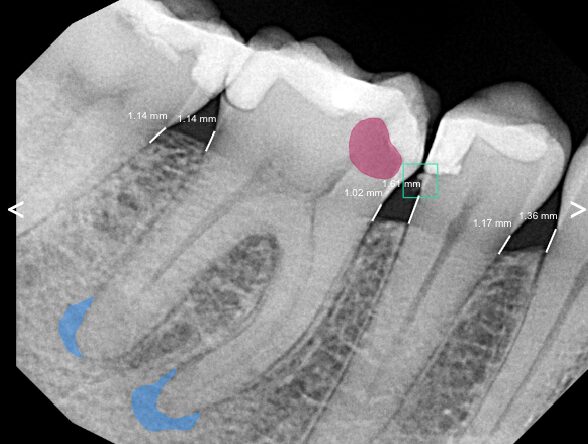

We’ll start by taking detailed images of your tooth to assess the extent of the damage and plan your treatment. Then, we’ll gently remove the decay and create a small opening in the crown of the tooth to access the pulp chamber. After that, we’ll carefully clean, disinfect, and shape the root canal before sealing it to prevent future infection—preserving your natural tooth and relieving your pain.

We’ll take pictures of your teeth to understand the extent of the damage and create a care plan. Next, we’ll remove the decay—saving the tooth—and create an opening in the tooth’s crown to the pulp chamber. Then, we’ll clean and reshape the canal, hermetically sealing it against future infection when we’re finished.